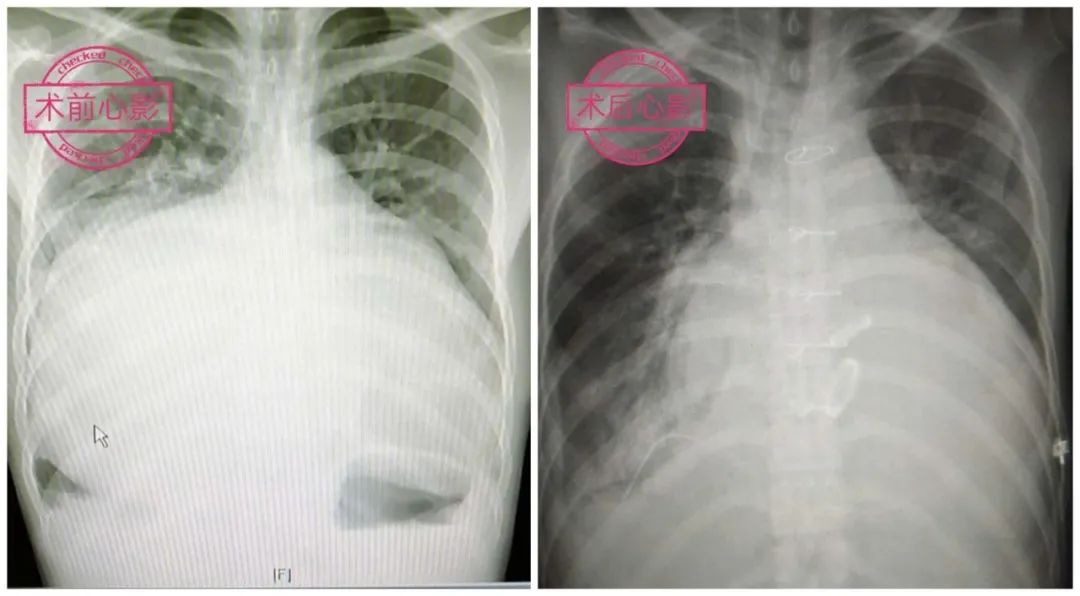

右心室流出道呈管型,肺动脉膜性闭锁(图1,主肺动脉发育正常,肺动脉